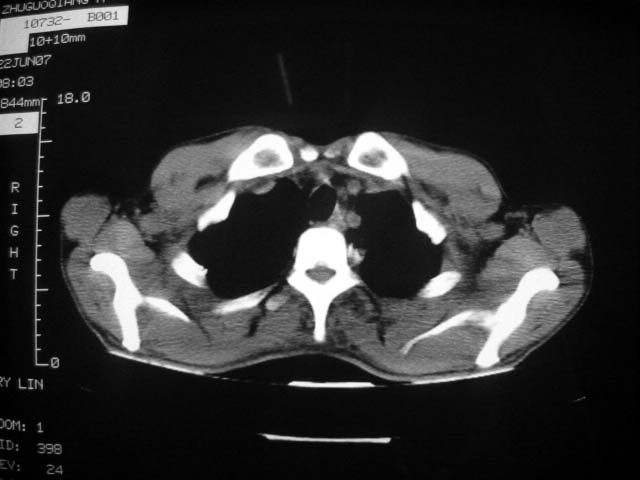

从ct7988c 至今未用任何抗生素及抗痨药,维持保肝治疗。患者低热、咳血渐消失。

07年6月22号复查

前几次大家认为是转移癌,但此次复查病灶却明显吸收好转,不支持诊断。请大家讨论。[emb10]

患者现无咳嗽咳痰及咳血,肝功好转,血清白蛋白降低,球蛋白升高,白球比小于0.5.少量腹水。

根据前后片比较应该考虑迁徙性肺脓肿,回帖相差甚远是因为前后片变化太大出乎大家意料之外,这就是影象诊断要结合临床复查对比的必要性,

回顾既往片,病变明显吸收,缩小,未经治疗,不支持肺转移瘤,可能为肺结节病或韦格氏肉芽肿